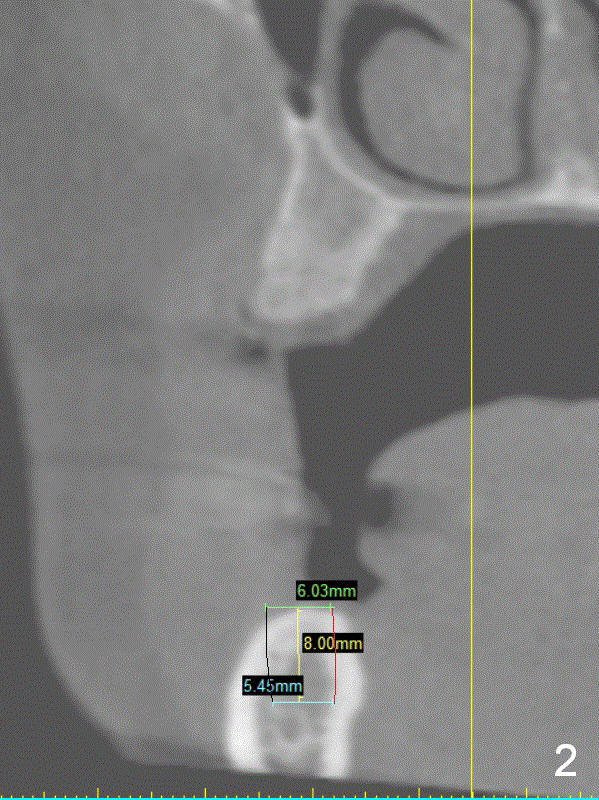

A 49-year-old lady is petit.  The crest at #30 is narrow.  A small implant is placed.  To increase its longevity, the patient should have left 1st molar occlusion.   Bone density at #19 is D1 (the cortex), D4 (upper medulla) and D3 (lower medulla) (Fig.1).  Bone is wide enough to hold a 6 mm (in diameter) implant, but a 8 mm long implant appears to be too long (Fig.2).  Therefore, a 6 or 6.5x6 mm implant appears to be appropriate (Fig.3).  How about the bone at #14?